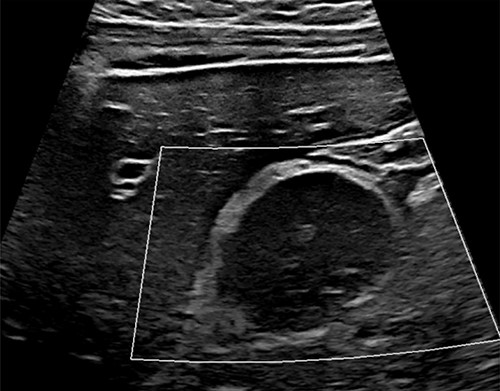

An abdominal ultrasound (US) demonstrated a peripancreatic cystic mass with internal debris located between the stomach and pancreas (Fig. 1). The differential diagnosis at that time included a foregut duplication cyst, an infradiaphragmatic sequestration and a pancreatic cystic lesion. Given the unclear origin of this lesion, an abdominal magnetic resonance imaging (MRI) was obtained, which identified a T1 hypointense and T2 hyperintense rim enhancing 4.3-cm mass with surrounding edema and adjacent peripancreatic inflammation (Fig. 2).

Initial abdominal US; abdominal US demonstrating hypoechoic, peri-pancreatic mass between stomach and pancreas (white box).